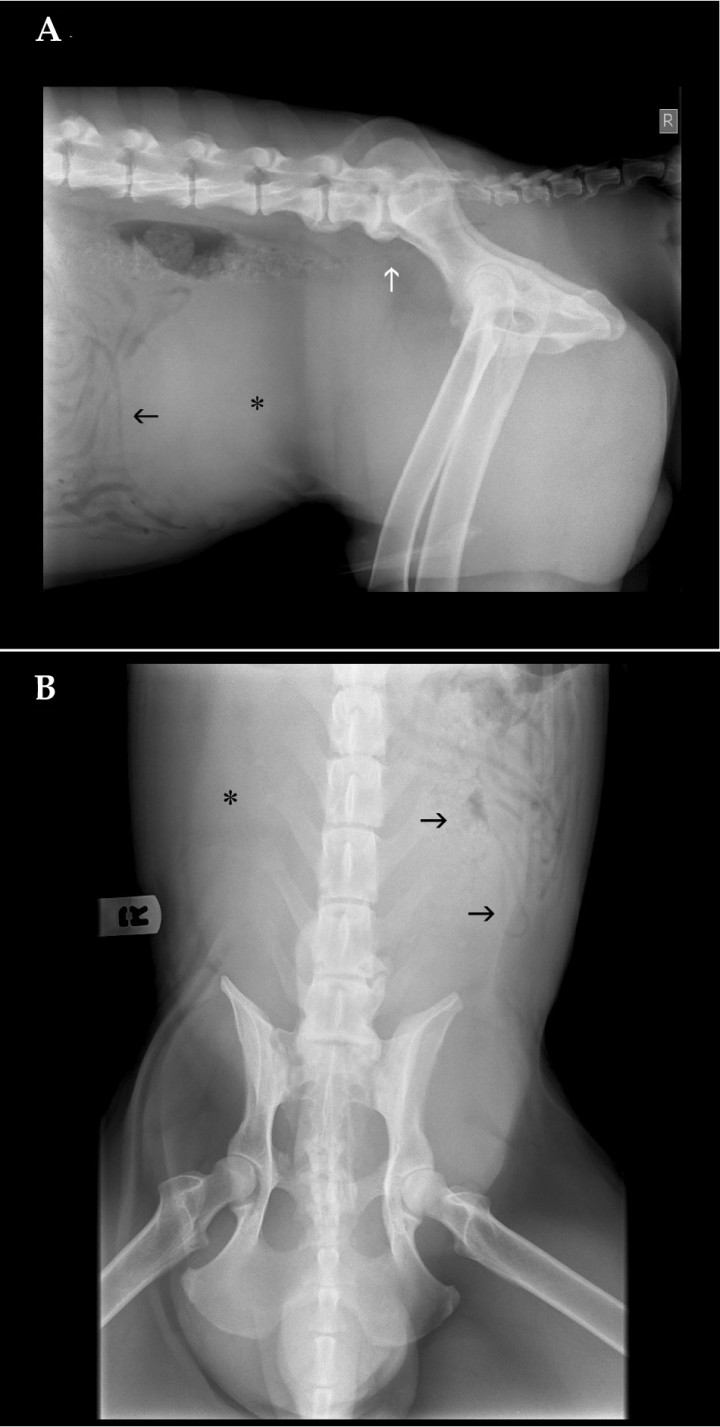

Se presentó en la consulta un perro de raza Weimaraner, macho no castrado de 3 años de edad, por una protrusión de la zona perineal izquierda, así como una historia de disuria y estreñimiento crónico desde hace una semana. En el examen físico se apreció distensión abdominal. Se hizo un estudio radiológico del abdomen, con proyecciones lateral derecha (Fig. 1A) y ventrodorsal (Fig. 1B).

<p>(<strong>A</strong>) Proyección lateral derecha. (<strong>B</strong>) Proyección ventrodorsal de abdomen de un perro de tres años de edad que se presenta con historia de disuria, estreñimiento y protusión perineal.</p>

Figura 1

(A) Proyección lateral derecha. (B) Proyección ventrodorsal de abdomen de un perro de tres años de edad que se presenta con historia de disuria, estreñimiento y protusión perineal.

Se visualiza una masa redondeada de opacidad tejido blando ocupando el abdomen caudal desde L4 a L7, además de pérdida de definición de serosas. Produce efecto masa con desplazamiento craneal y hacia el lado izquierdo de asas intestinales, así como desplazamiento dorsal del colon descendente, produciendo una estenosis de su luz a nivel de L7 que se continúa caudalmente hasta la primera vértebra coccígea (Fig. 2A y 2B). Además, se visualiza una estructura de opacidad tejido blando que se extiende desde abdomen caudal hacia el canal pélvico, protruyendo hacia la región perineal. Puede observarse también osteoartrosis a nivel de L6-S1 (Fig. 2A).

<p>Mismas imágenes que en Figura 1. (<strong>A</strong>) Proyección lateral derecha. Se observa una estructura de opacidad tejido blando ocupando el abdomen caudal (asterisco), con desplazamiento craneal de las asas intestinales (flecha negra) y desplazamiento dorsal del colon descendente, produciendo estenosis de su luz a nivel de L7 (flecha blanca). (<strong>B</strong>) Proyección ventrodorsal. Al igual que en la proyección lateral, se observa la misma estructura de opacidad tejido blando (asterisco), así como el desplazamiento de las asas intestinales (flechas negras).</p>

Figura 2

Mismas imágenes que en Figura 1. (A) Proyección lateral derecha. Se observa una estructura de opacidad tejido blando ocupando el abdomen caudal (asterisco), con desplazamiento craneal de las asas intestinales (flecha negra) y desplazamiento dorsal del colon descendente, produciendo estenosis de su luz a nivel de L7 (flecha blanca). (B) Proyección ventrodorsal. Al igual que en la proyección lateral, se observa la misma estructura de opacidad tejido blando (asterisco), así como el desplazamiento de las asas intestinales (flechas negras).